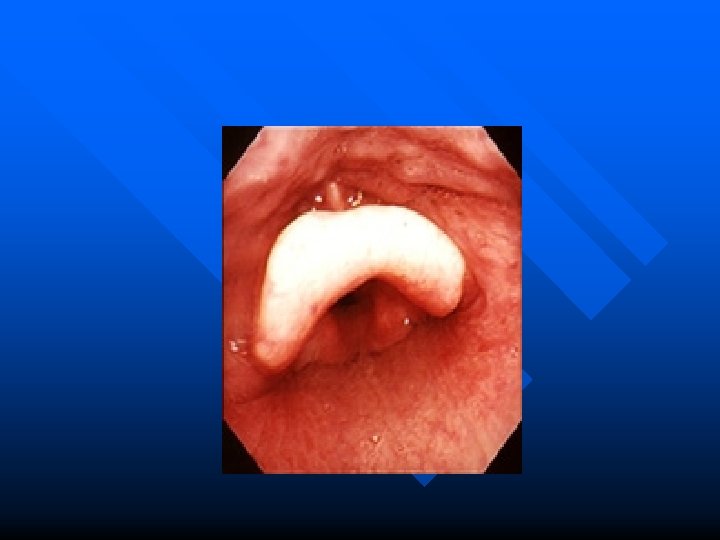

Epiglotite Aguda n n Maior incidência em pré-escolares Sintomas: – – – n Dor na orofaringe Obstrução da via aérea Febre Disfagia Estridor e Rouquidão Diagnóstico – Exame direto e Radiológico n Tratamento – IOT – ATB (H. influenzae) + Dexametasona